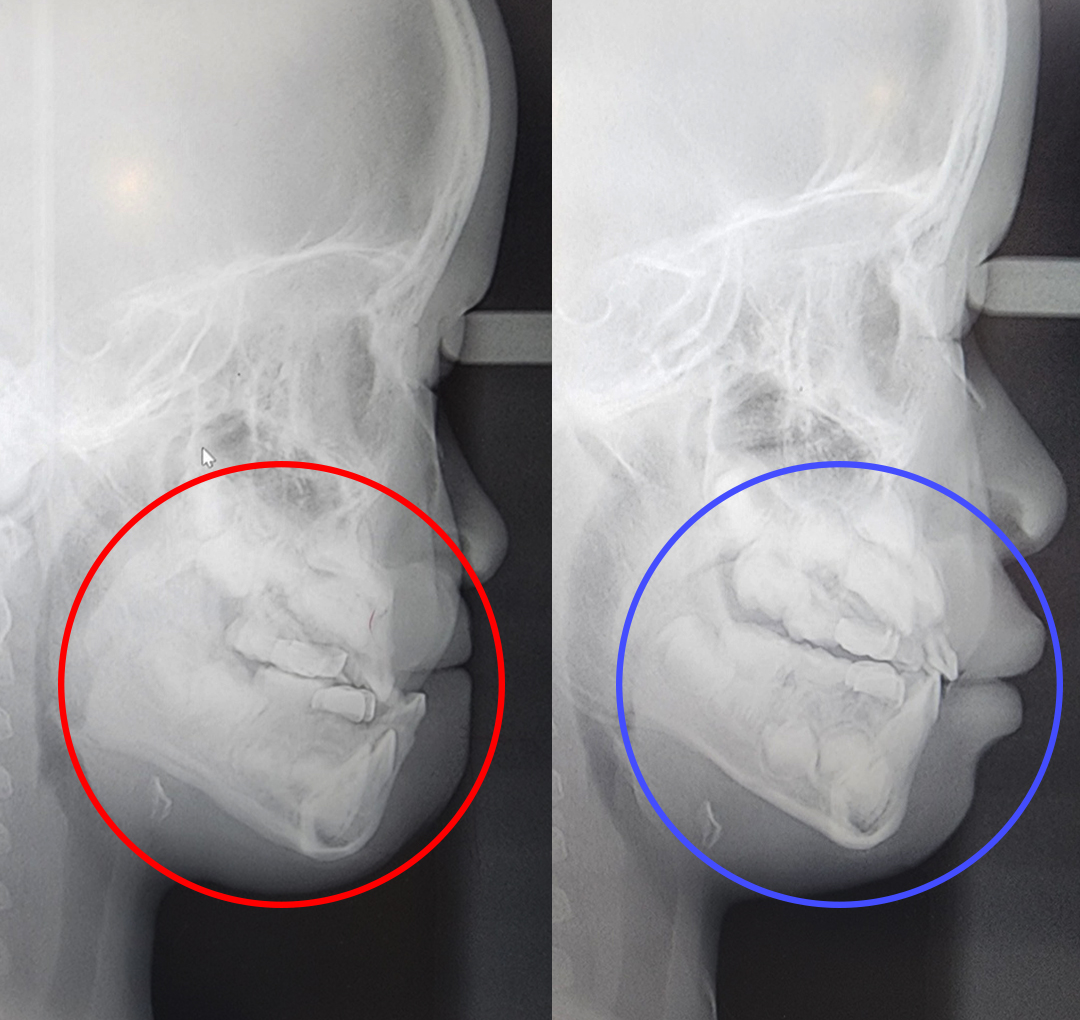

프랑켈장치 교정

어린이 3급 부정교합 & 프랑켈장치 교정

구호흡을 지속적으로 하게 되면 아래턱이 하방 성장하면서 아래 앞니가 위 앞니를 덮는 부정교합이 될 수 있습니다.

프랑켈장치 교정.

어린이의 치아와 턱뼈를 정상 위치에서 정상적으로 성장할 수 있도록 도와주는 치료 방법입니다. 프랑켈장치 교정은 영구치가 나오기 전, 유치 때부터 일찍 치료하여 편하게 정상교합이 될 수 있습니다. 프랑켈장치 교정은 만 3~12세에 가능하지만 만 4~6세에 치료를 시작하면 좋습니다.

- 5주걱턱과 양악수술을 예방할 수 있습니다.